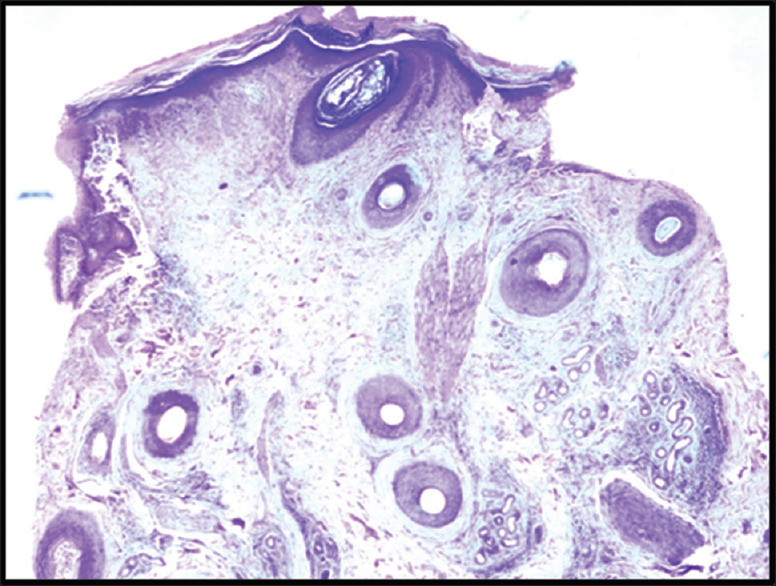

Materials and methods: This cross-sectional study was conducted over a period of 1 year in the department of dermatology and pathology in a tertiary care hospital in North India. Adult patients (age >18 years) presenting with patchy cicatricial alopecia as well as clinically doubtful noncicatricial conditions over the scalp were included in this study. In doubtful cases of noncicatricial alopecia, a single 4-mm punch biopsy was performed for transverse sectioning with hematoxylin and eosin stain. In all cases of cicatricial alopecia, two 4-mm punch biopsies were performed, one for transverse sectioning and the second for vertical sectioning and direct immunofluorescence (DIF). The final diagnosis was made on the basis of the trichopathologic findings.

Results: A total of 23 cases were included in our study with the majority (52.2%) being in the age group of 20-30 years. The mean age at diagnosis was 30.5 ± 11.38 years. On the basis of trichopathologic findings, a final diagnosis was made in 18 (78.3%) cases. However, 5 (21.7%) cases remained undiagnosed and were labeled as nonspecific. According to the final diagnosis based on the trichopathologic findings, maximum cases were of discoid lupus erythematosus (DLE) (26.1%), followed by lichen planopilaris (21.7%), pseudopelade of Brocq (13%), alopecia areata (8.7%), folliculitis decalvans (4.3%), and traction alopecia (4.3%). Trichopathologic examination revealed hyperkeratosis (60%), basal cell vacuolization (55%), epidermal atrophy (55%,) perifollicular lymphocytic infiltrate (30%), pigment incontinence (30%), perifollicular fibrosis (25%), and thickened basement membrane (25%). Only four cases showed deposits of immunoreactants in DIF and all four were finally diagnosed as DLE.